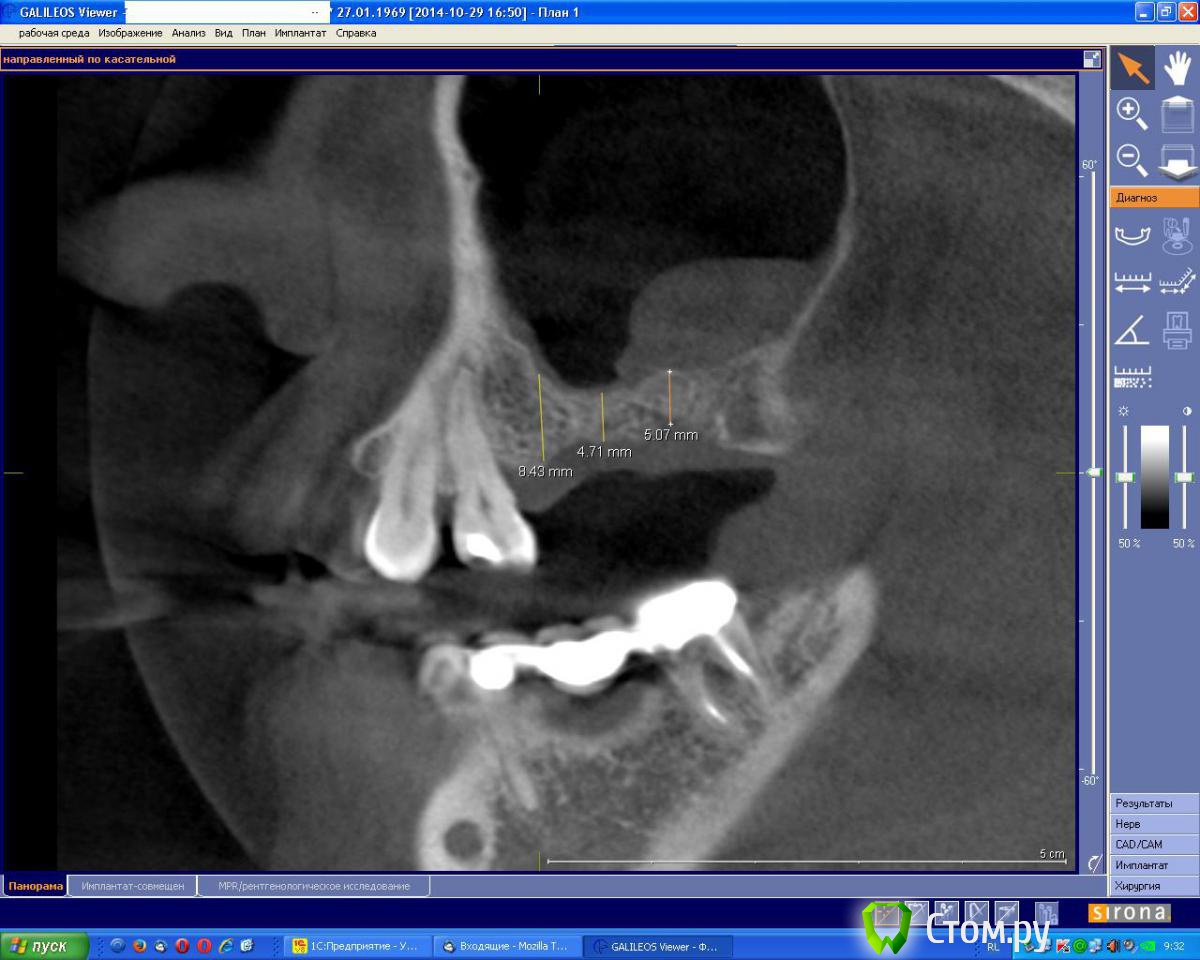

an_ver Опубликовано 1 ноября, 2014 Поделиться Опубликовано 1 ноября, 2014 Вот такой мешок увидел у пациентки.Вопрос: отправить к Лору а потом повторно КТ и открытый? Ссылка на комментарий

vesvova Опубликовано 1 ноября, 2014 Поделиться Опубликовано 1 ноября, 2014 Можно и без лора....Сразу на открытый.Но для точности, во фронтальной проекции посмотреть соустье.... Ссылка на комментарий

an_ver Опубликовано 1 ноября, 2014 Автор Поделиться Опубликовано 1 ноября, 2014 Открыто 1 Ссылка на комментарий

kriokov Опубликовано 2 ноября, 2014 Поделиться Опубликовано 2 ноября, 2014 an_verфронтальный срез классный залили, все что надо видно Ссылка на комментарий